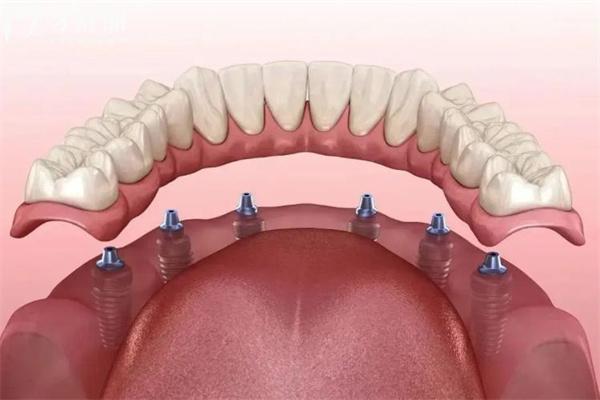

半口种植是很多缺牙朋友关心的一个问题。到底“半口种植是几颗牙齿?”这是个看似简单却不太固定的答案,得结合个人口腔条件和缺牙范围来说。

半口种植牙齿的数量其实没有统一的标准,通常来说一般在4颗到8颗之间浮动。为什么这么说?关键在于“半口”的定义——通常指的是一侧上下颌的牙齿缺失,也就是一边牙齿的全部或者大部分缺失。

在传统种植修复中,为了确保咀嚼功能和美观,医生会根据缺失牙齿的数量、牙槽骨的状况、患者咬合关系等多重因素,定制合适的种植方案。通常采用4颗种植体支撑半口牙冠修复,部分病例可能需要5颗、6颗甚至8颗种植体才能达到理想结果。

医生技术与种植体系不同医生和不同种植系统的方案设计也会影响种植颗数。比如,采用All-on-4技术的患者,半口只需要4颗种植体就能支撑整排牙齿。

All-on-4方案这种方案在半口种植中非常受欢迎。只需4颗种植体,就能完成半口或全口牙齿的固定修复,既节省成本又缩短手术复原时间。All-on-4的关键是通过斜向种植增强骨结合面积,确保种植稳定。

传统多颗种植根据缺牙数目,可能需要5-8颗种植体分别种植,再通过牙冠桥连成整体。此方案适合骨质条件较好,追求长期稳定的患者。